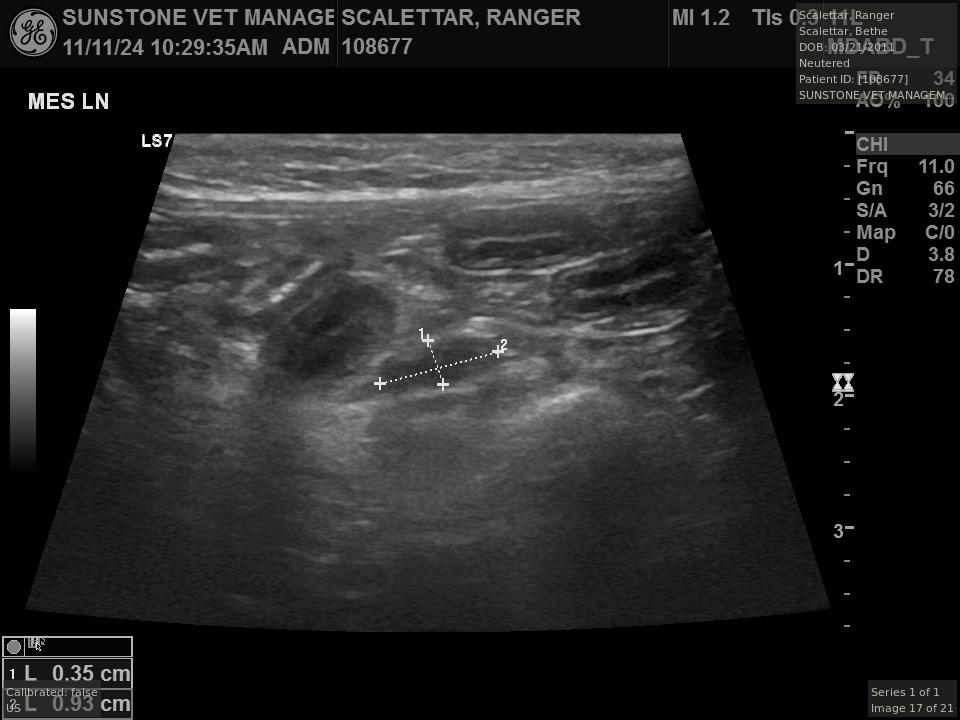

The veterinarian generated a series of images showing different organs and substructures by

changing the position and orientation of the ultrasound transducer. The images were collected

in a defined order, which is repeated from patient to patient, ensuring that nothing is missed. In

Ranger's case, the sonographer collected about twenty images during an examination that

lasted about fifteen minutes.

The sonographer stated that Ranger's ultrasound images were largely normal for an older cat. In particular, they show changes in the kidneys that are commonly noted in geriatric cats and that reflect a risk for the development of chronic kidney disease. However, the images did not show any significant abnormalities in Ranger's stomach, intestines, and associated lymph nodes. Nonetheless, the results did not rule out recurrence of Ranger's small cell lymphoma.